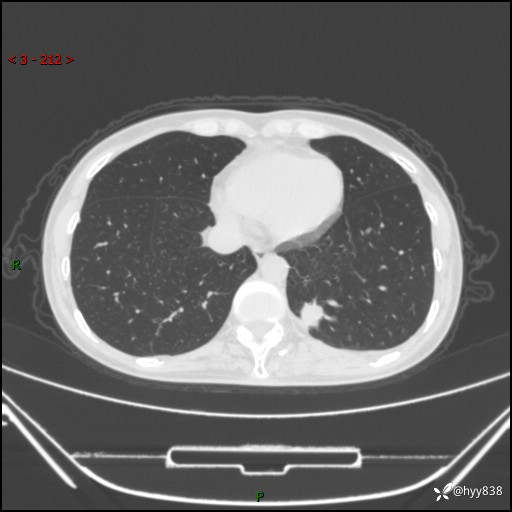

胸部CT平扫

增强动脉期+静脉期

各期CT值:48hu 65hu 76hu